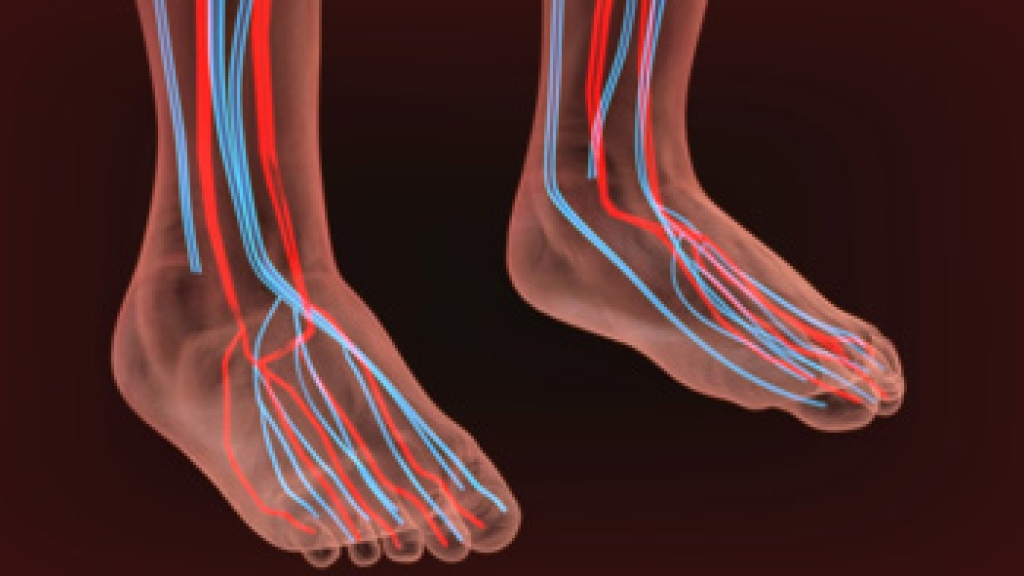

Reasons for Burning Foot Pain

Peripheral Vascular Disease – can restrict the blood flow to the feet, and often times lead to amputation of the feet.